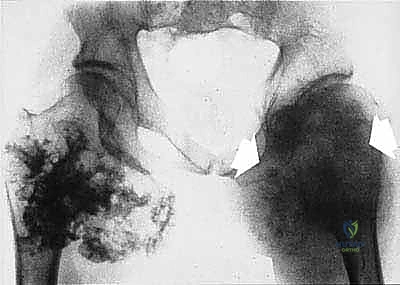

* الساركوما العظمية (Osteosarcoma): الأكثر شيوعاً، تظهر عادة حول الركبة (أسفل الفخذ أو أعلى القصبة).

| حدود الورم في الأشعة | واضحة، محددة بدقة (Sclerotic margin) | غير واضحة، متآكلة (Moth-eaten appearance) |

| اختراق قشرة العظم | نادر جداً | شائع جداً، يمتد للأنسجة الرخوة المحيطة |